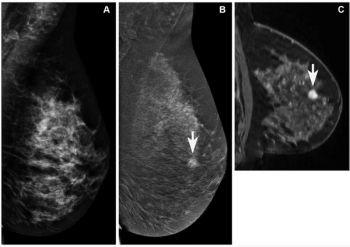

In findings from an enriched cohort of asymptomatic patients with screening-detected abnormalities, researchers found that contrast-enhanced mammography (CEM) was superior to conventional mammography and offered equivalent detection of breast cancer in comparison to breast MRI and abbreviated breast MRI.